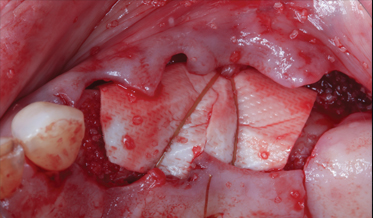

Use of Tuberosity Tissue Block for Tunneling Reconstruction of Class III Sockets With Simultaneous Implant Placement: A Case Report